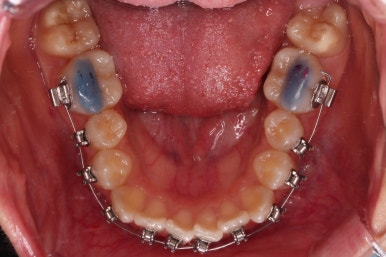

그리고 왼쪽 하단의 사진에 화살표를 보시면, 예전에 신경치료를 해둔 치아인데 어린 나이에 신경치료를 하다보니 크라운으로 치료를 마무리 하지 못했어요.

그래서 기성품을 딸깍 끼워두든지, 위의 화살표 사진처럼 구멍을 떼워두게 돼요.

신경치료 되었던 화살표 치아는 그새 더 썩어 일부 부러지기까지 하여 교정 마무리 전까지 버티게끔 임시치아로 감싸주기로 했어요.